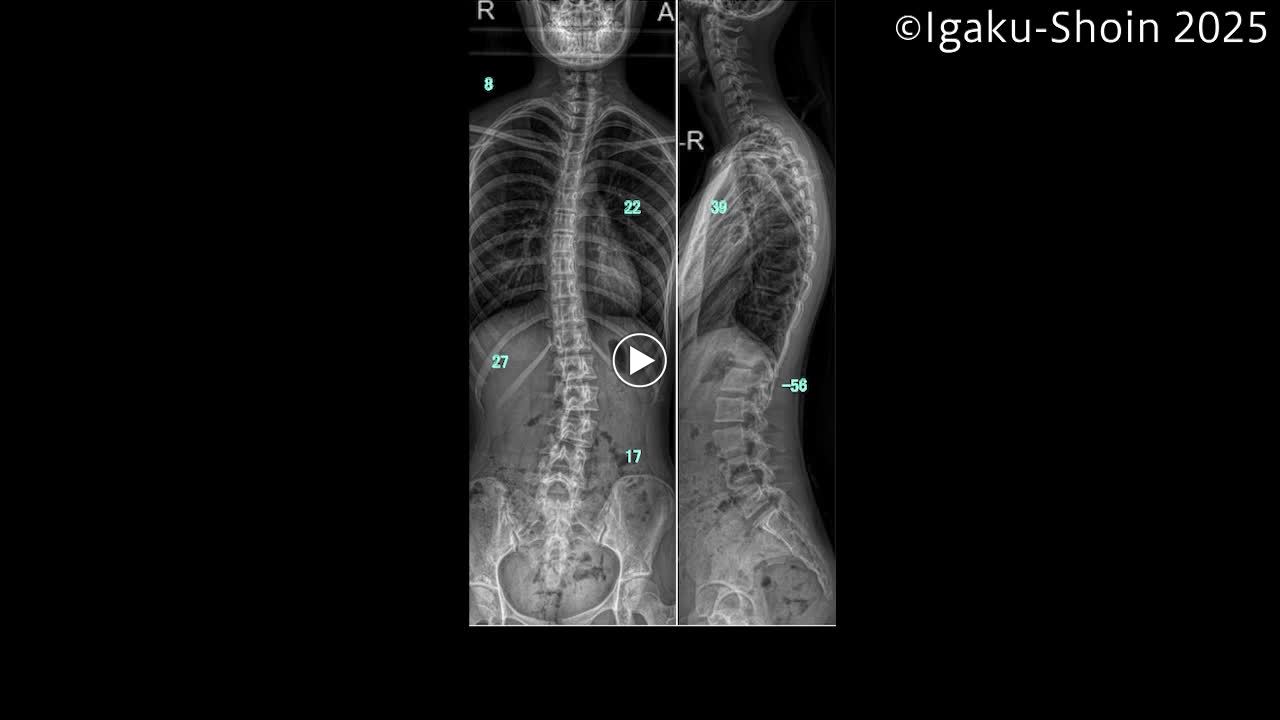

動画38 Corrective PLIFの手術